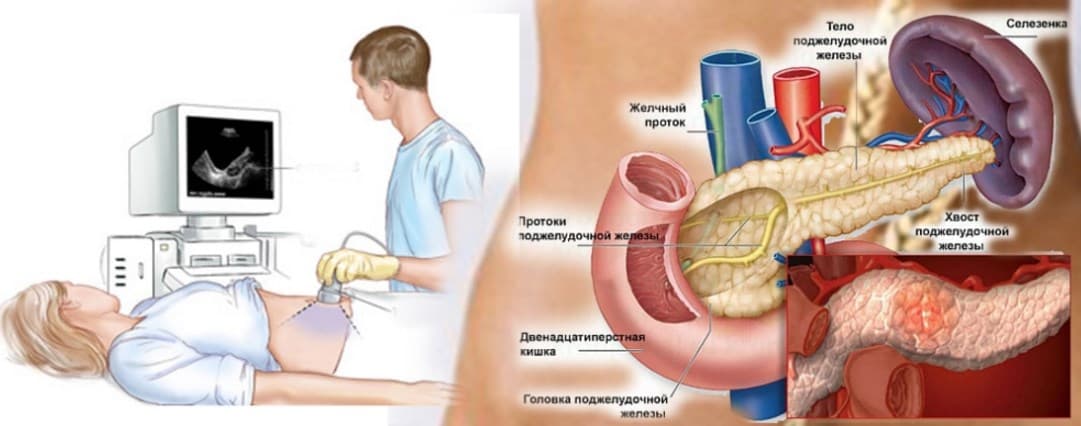

Диагностические мероприятия

Лечение врач назначает после подробной диагностики. При болевых приступах в первую очередь проводится внешний осмотр пациента.

Затем назначается обследование:

- УЗИ брюшной полости, информативное обследование, дающее врачу сведения о структуре, контурах ПЖ, проходимости протоков, наличии конкрементов;

- Рентгенография проводится для получения таких же сведений;

- КТ или МРТ, они дают более точные сведения о состоянии всех органов, связанных с ПЖ.

Обследование на аппаратах УЗИ, КТ, МРТ дают фото, по которому четко видно состояние всей железы и прилегающих органов и тканей.

Боли в железе, в связи с ее сложным анатомическим расположением, часто путают с симптомами других патологий пищеварения, поэтому обследование необходимо для четкой конкретизации воспаления ПЖ. Все обследование и дальнейшее лечение проводится под контролем гастроэнтеролога.